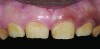

Figure 16. Anterior final restorations bonded.

Figure 16

The anterior restorations were fabricated with low-translucency lithium-disilicate ingots and layered in the incisal half to provide the desired internal characteristics in accordance with the patient’s age. The final anterior restorations were then tried-in and verified for marginal fit, esthetics, and phonetics. After the patient’s approval, they were bonded using dual-cured resin cement (Variolink® II, Ivoclar Vivadent) (Figure 16). Because the enamel in such cases is already compromised, bonding can become clinically unpredictable. A self-etching primer was used on the teeth, followed by a bonding agent (Clearfil™ ST Bond, Kuraray Dental, www.kuraraydental.com) that was light-cured for 20 seconds. The intaglio of the crowns was prepared by etching with 9% buffered hydrofluoric acid for 60 seconds and silanating them to achieve optimum bonds to the resin cement.18